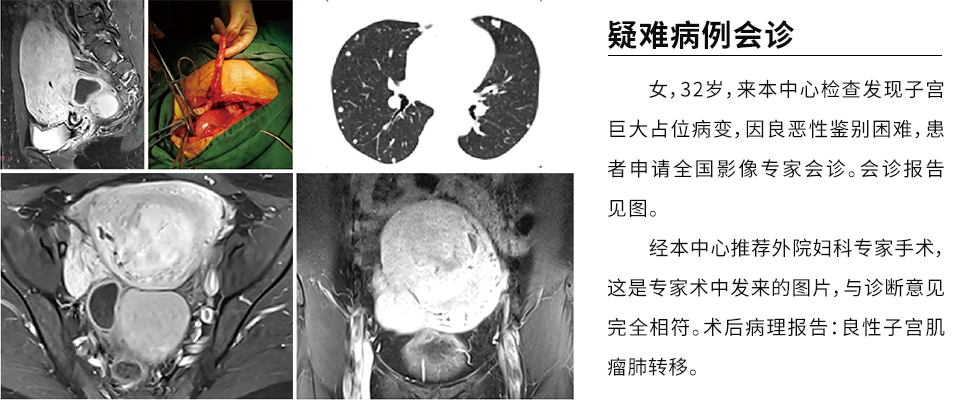

See the film diagnosis for you